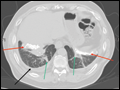

| Figure e34-32 Three examples of air bronchograms (red arrows) on chest CT. | |